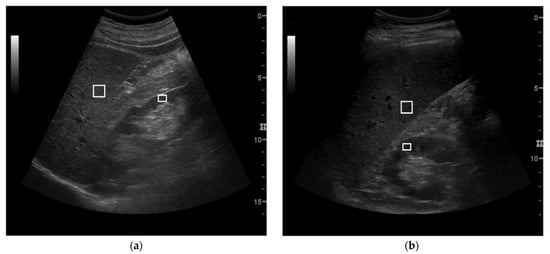

2.2. US Examination